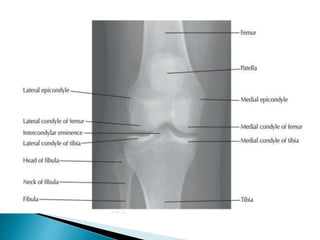

 The normal anatomical load-bearing axis of

the knee is viewed as ranging from 5 to 7

degrees of valgus and approximately 60% of

the weight-bearing force is thought to

transmit through the medial compartment

and 40% through the lateral compartment